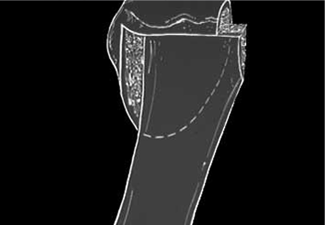

Tratamiento de rescate del Hallux Valgus artrósico o secuelar mediante fijación o artrodesis.